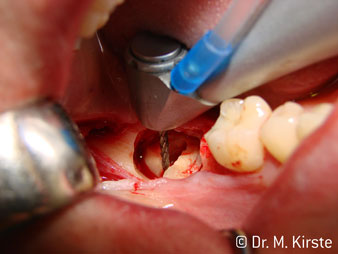

Elegir el ángulo de 45º ofrece múltiples ventajas de uso. Los odontólogos dedicados a cirugía (para quienes se desarrolló principalmente esta pieza de mano) se percatarán de inmediato de que se puede trabajar de forma muy específica. En especial en la remoción de las muelas del juicio (Fig. 2), no es necesaria una gran abducción de las partes blandas en la zona del carrillo (Fig. 3). El diseño del cabezal de la pieza de mano, combinado con los suaves giros del cabezal durante la preparación, permite trabajar de forma rápida y segura en la zona retromolar.

Acerca del trabajo rápido: puede conseguirse una velocidad de más de 100.000 rpm. Una refrigeración absolutamente profesional y un pequeño cabezal resuelven cualquier duda sobre los efectos térmicos o el trabajo con buena visibilidad.

El nuevo diseño de los rodamientos dentro del cabezal de la pieza de mano garantiza el funcionamiento silencioso de la fresa, en la separación del diente o la raíz (Fig. 4-9) se muestra una impresionante imagen de corte sin efectos de impacto.

El contra-ángulo de 45º se adapta muy bien a la mano. Es fácil darse cuenta de que el cabezal de trabajo sigue el ángulo del dedo índice y, así, el movimiento deseado solo se desplaza unos centímetros en paralelo a la punta (Fig. 1)."